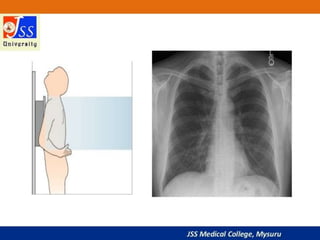

Chest X-rays are commonly used medical imaging tests that produce images of the structures and organs inside the chest such as the heart, lungs, blood vessels, and soft tissues. They can be used to diagnose conditions like pneumonia, lung cancer, and heart failure by detecting abnormalities in these structures. Chest X-rays expose patients to a very small dose of ionizing radiation but provide valuable medical information to guide diagnosis and treatment.